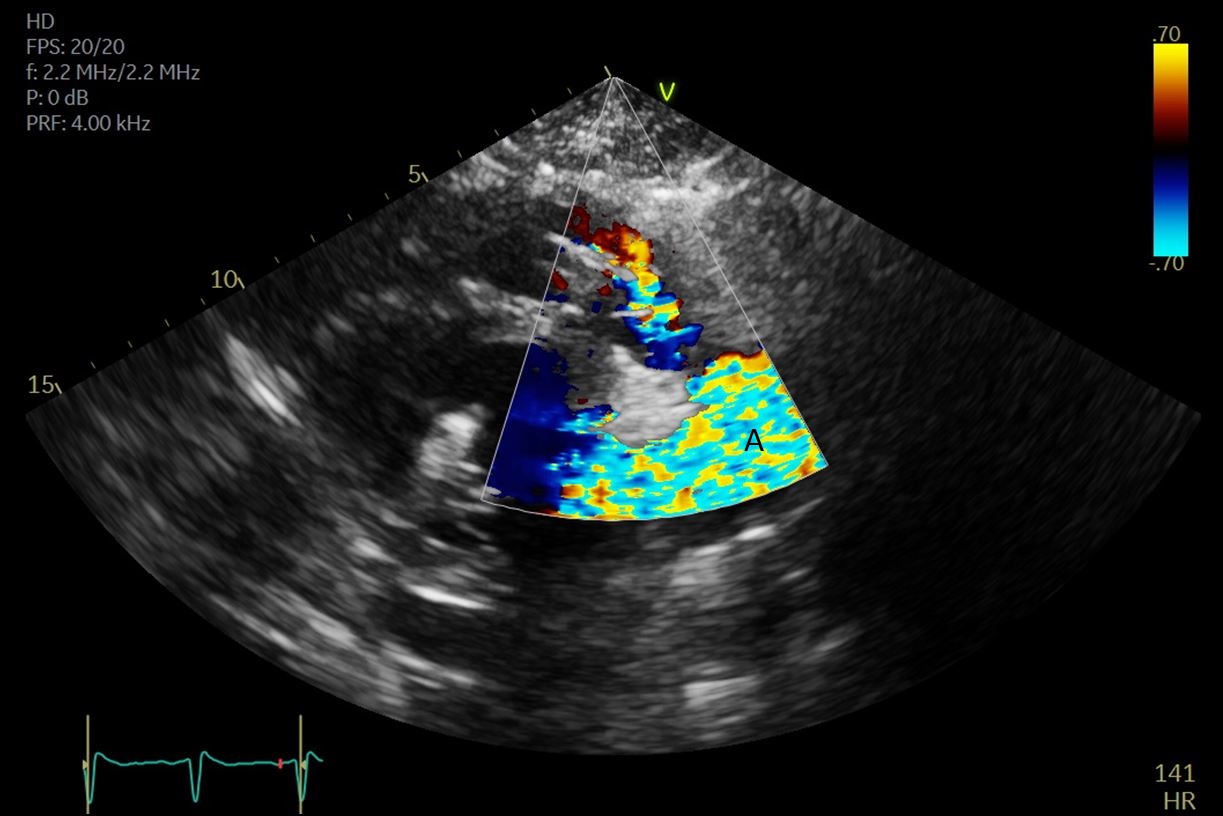

Both TTE and TEE can help with ideal positioning of the Impella (Figs. 5,6). The distance from the aortic valve to the Impella inlet should be measured. This should ideally be 3.5–4 cm for all Impella devices except for the Impella 5.5 for which it is 5 cm [15] (Fig. 7). The outlet should be 1.5–2 cm above the sinuses of Valsalva. The catheter should be angled towards the LV apex and away from the septum and mitral valve. The positioning of both the inlet in the LV cavity and the outlet above the aortic valve should be confirmed. Color flow doppler imaging can help confirm this positioning as a mosaic pattern will be visualized near the inlet and outlet ports on spectral doppler (Fig. 8). Real-time 3D echocardiography can also be used to help in visualizing Impella positioning relative to other anatomical structures (Fig. 9). After placement of the Impella, the aortic and mitral valves should be interrogated for any new or worsening regurgitation or dysfunction [16]. TEE can also help identify additional complications of Impella placement including pericardial effusion or LV free wall rupture [17].

Fig. 5.A midesophageal 4 chamber view on TEE demonstrating an Impella traversing the aortic valve with the inflow port in the left ventricle. (A) Left Atrium. (B) Left Ventricle. (C) Impella.